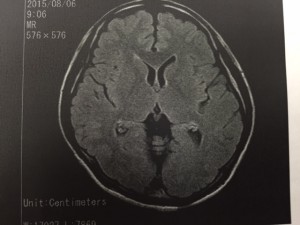

実は私、頭痛持ちなんです。最近の人は皆そうですよね。私は睡眠不足だし、不摂生で当然のことだと思います。私の場合は、閃輝暗点(せんきあんてん)といって眼がチカチカし始めると頭痛が酷くなるパターンです。昔からなので気にもしませんが、最近は本当に酷いです。なかなか病院に行く時間も取れず、ずっと我慢してましたが・・・限界。なんとか病院に行き検査をうけました。とても健康な脳でした。とても健康です。いつも通り偏頭痛という診断です。しっかり偏頭痛と向き合わないといけませんね。